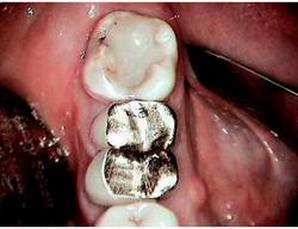

Conversely, let’s get back to the implant patients who will be missing teeth. This is significant for all general practitioners who have ever gotten the emergency patient call stating that their crown has “come off.” Undoubtedly, the patient presents (usually late on a Friday afternoon!) with the crown, buildup, and probably some natural tooth in hand. Now comes your moment of truth. Do you assume the role of “Super-Dentist” trying to retrofit the crown over no remaining ferrule, while hoping that the patient pays their bill and never returns to your office for fear of the “crown falling off” again? Or, do you begin the educational process, based upon science and predictable results, to guide your patient through understanding the problem that they have?

The education begins with showing the patient how the lack of remaining tooth structure makes any dental heroics unpredictable and economically unsound. We all need to respect the fact that even in a perfectly balanced occlusion, the prognosis of that “tired tooth” rebuilt with endodontic treatment, posts, cores, pins and crowns, in the absence of remaining natural tooth structure (ferrule), will in fact fail. It is just a matter of time. Once the educated patient accepts the futility of “the old standard of care,” they are now more open to understanding the “new standard of care”—dental implants.